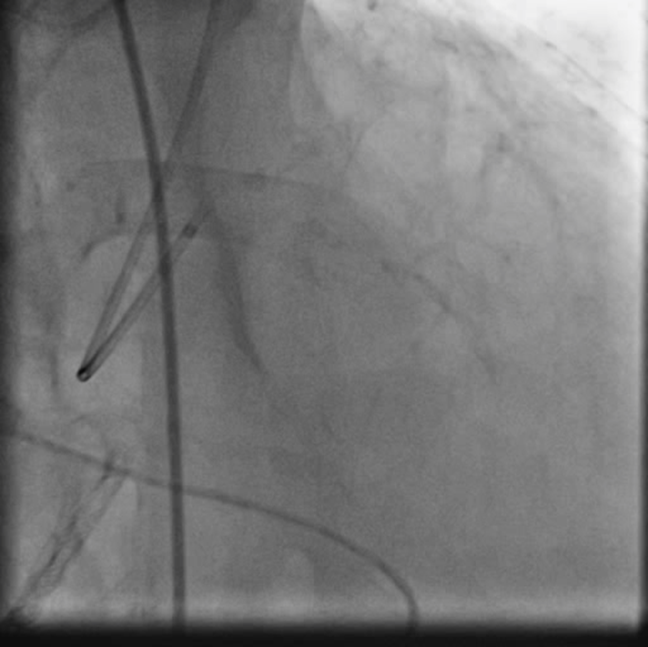

PCIof right coronary artery was initiated on IABP support with amplatz left1 guided catheter and vessel was crossed with great difficulty in repeatedattempts by fielder XT followed by GAIA 2 wire over corsair microcatheter. Microcathetercould not be crossed beyond mid segment calcified CTO, so balloon dilation with0.75 mm balloon was done after which again microcatheter could not be trackedbeyond mid part. Butwe were able to exchange wire to allstar followed by rotawire byplacing microcatheter in mid segment after balloon dilation by 0.75 mm balloon. Rotablation wasdone with 1.25 mm burr at 1,60,00 rpm repeatedly from proximal to mid distalpart. Lesionstill looked unprepared as repeated postdilation with2.25*15 mm followed by 2.5*15 mm non compliant balloon at high pressures showedunexpanded balloon. Againlesion preparation was done with 2.5*15 mm wolverine cutting balloon repeatedlyat high pressures which led to adequate luminal gain and calcium cracks as seenon IVUS run. AfterIVUS run again high pressure balloon dilation was done with wolverine 2.5*15 mmballoon followed by 2.5*12 mm non compliant balloon at 28 atm toadequately prepare the lesion before stent deployment. Stentingwas done with 2.5*32 mm DES, 2.75*32 mm DES, and 3*24 mm DES from distal toproximal in overlapping fashion. Thenfinally high pressure post dilation was done with 2.75*15 mm followed by 3*15mm non compliant balloon and adequate stent expansion was achieved with TIMI 3 flow.